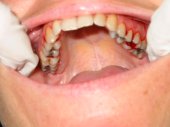

Alteraciones de los tejidos parodontales (encía, ligamento y hueso) por problemas funcionales |

Sangrado gingival espontáneo, infecciones

en las encías o movilidad dentaria debidos al desequilibrio oclusal